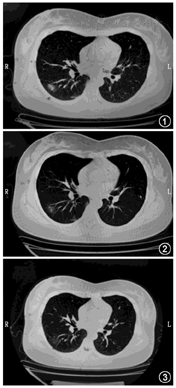

服药初期有乏力等临床症状,服药期间未出现发热等其他不适,服药5 d后临床症状明显缓解。服药7 d后稍有呼吸胸痛,后明显缓解,病情未见反复。2月4日因个人原因暂停继续服药,2月7日出院时在基础方的基础上调整部分药物剂量加入陈皮、枳壳各10 g,带药5剂出院,2月9日电话随访无特殊不适。1月21日确诊CT因个人原因,无法取得影像资料。复查CT见图1,图2,图3,服药后CT显示在第7天可见感染灶明显吸收,显效。